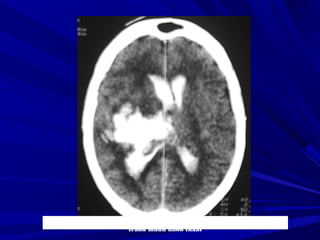

XUAÁT HUYEÁT

NAÕO

Phát hiện xuất huyếtPhát hiện xuất huyết

Xuất huyết là các vùng tăng đậm độ và có thể thấyXuất huyết là các vùng tăng đậm độ và có thể thấy

trong các bệnh lý:trong các bệnh lý:

Tụ máu ngoài màng cứng,Tụ máu ngoài màng cứng,

Tụ máu dưới màng cứngTụ máu dưới màng cứng

Xuất huyết màng nãoXuất huyết màng não

Xuất huyết não thấtXuất huyết não thất

Xuất huyết trong nãoXuất huyết trong não

Phân biệt hoá vôi và xuất huyết nhỏ vùng nhân nềnPhân biệt hoá vôi và xuất huyết nhỏ vùng nhân nền